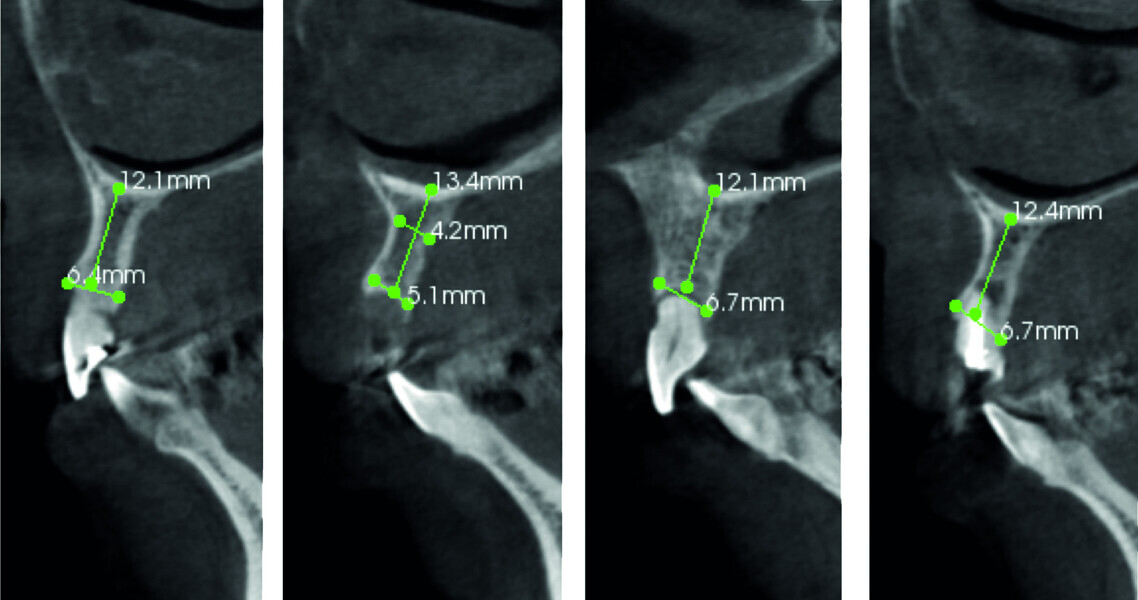

Fig. 4: Pre-op CT analysis.